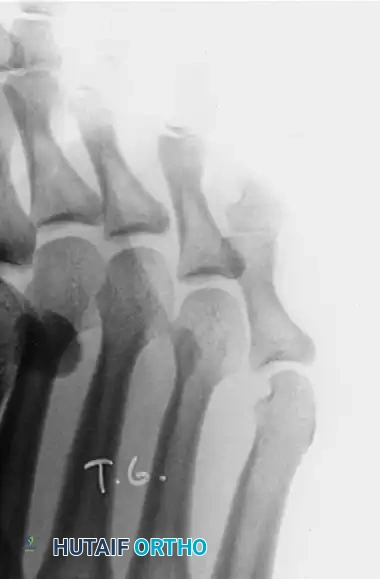

These lesions are almost exclusively located beneath the lesser metatarsal heads, most commonly the second or third. They are the direct result of a prominent plantar condyle of the metatarsal head driving into the plantar fat pad during the stance phase of gait.

As the prominent lateral or medial condyle of the metatarsal head creates focal pressure, the skin responds by forming a dense, conical keratotic wedge that points inward, causing severe sharp pain upon weight-bearing.

- Resection: Using a McGlamry elevator, the plantar plate is freed from the metatarsal head. A micro-sagittal saw is used to resect the prominent plantar condyle (usually the lateral condyle, as seen in the diagrams above) flush with the metatarsal shaft.